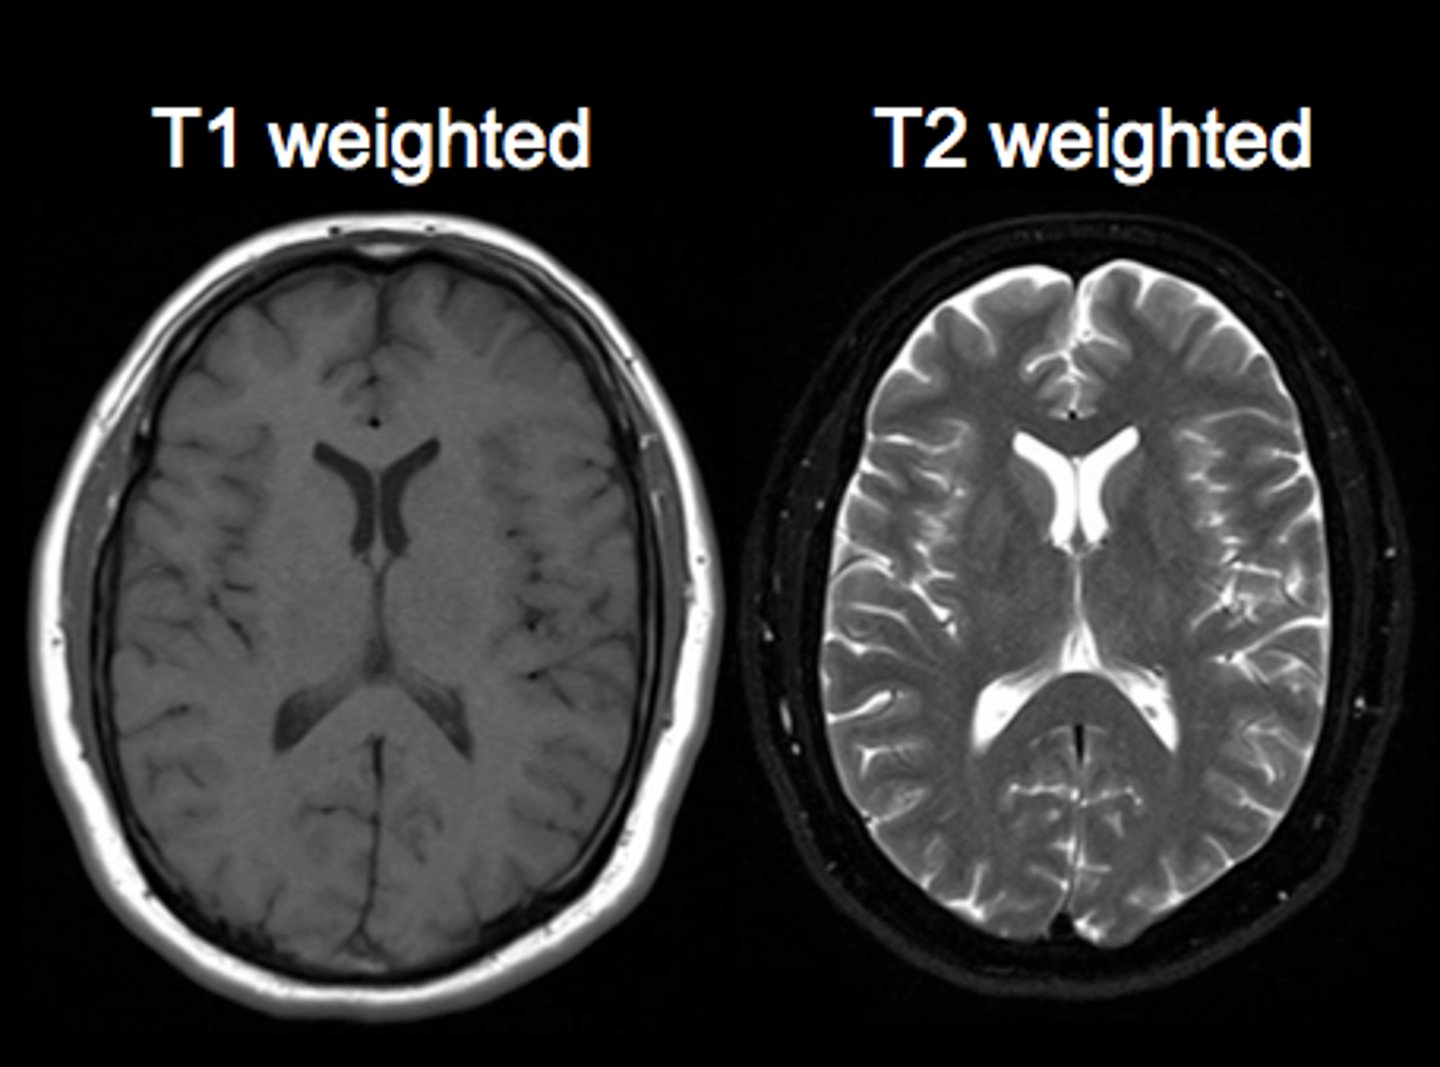

MRI T1 images

Fat is white

Water is dark

MRI T2 images

Fat is dark

Water is white